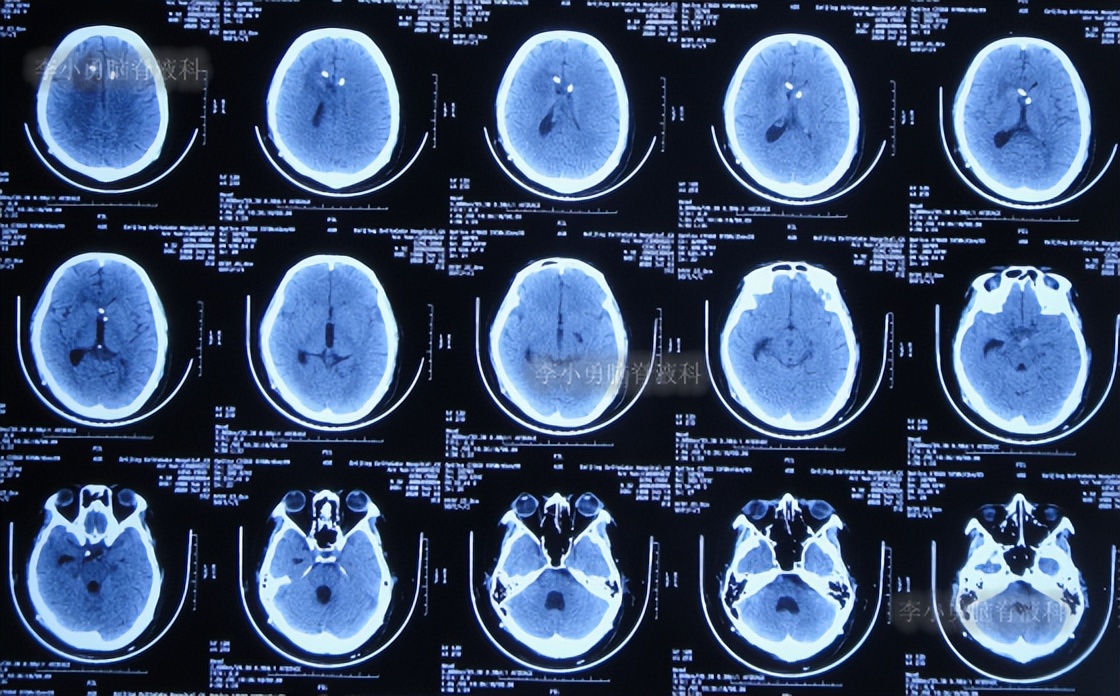

二、第1次在李小勇脑脊液科治疗过程和结果

2020年6月4日(脑囊虫切除术+第三脑室造瘘术后2年5个月,2次脑室腹腔分流术均堵管,期间历经5次住院但脑积水仍反复复发)住入李小勇脑脊液科,入院时:神志朦胧,饮食差,问答有误,自己站立不稳,双眼对视(图-19);既往史:口服抗癫痫药物,青霉素过敏。头颅CT示鞍上占位术后,脑室内可见引流管,脑室系统扩张(图-20)。

图-20:2020年6月4日头颅CT

入院后2天即2020年6月6日,进行了脑室腹腔分流管拔除术+脑室穿刺外引流术(图-21)。

图-21:2020年6月6日头颅CT

2020年6月8日(住院治疗4天),查头颅CT示脑室有所缩小,有少量积血(图-22),引流管培养出表皮葡萄球菌感染。

图-22:2020年6月8日头颅CT

2020年6月10日(住院治疗6天),查头颅CT示脑室缩小(图-23)。

图-23:2020年6月10日头颅CT